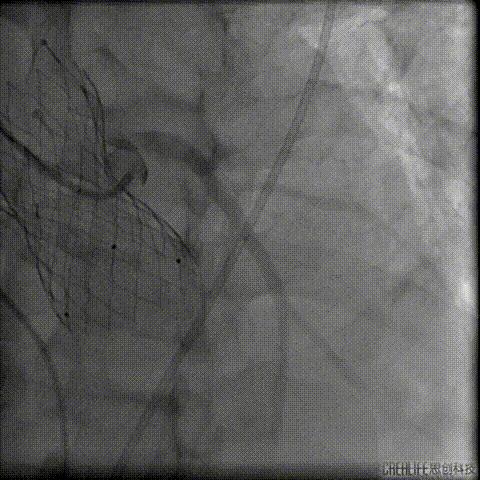

球囊压迫后植入覆膜支架

复查造影